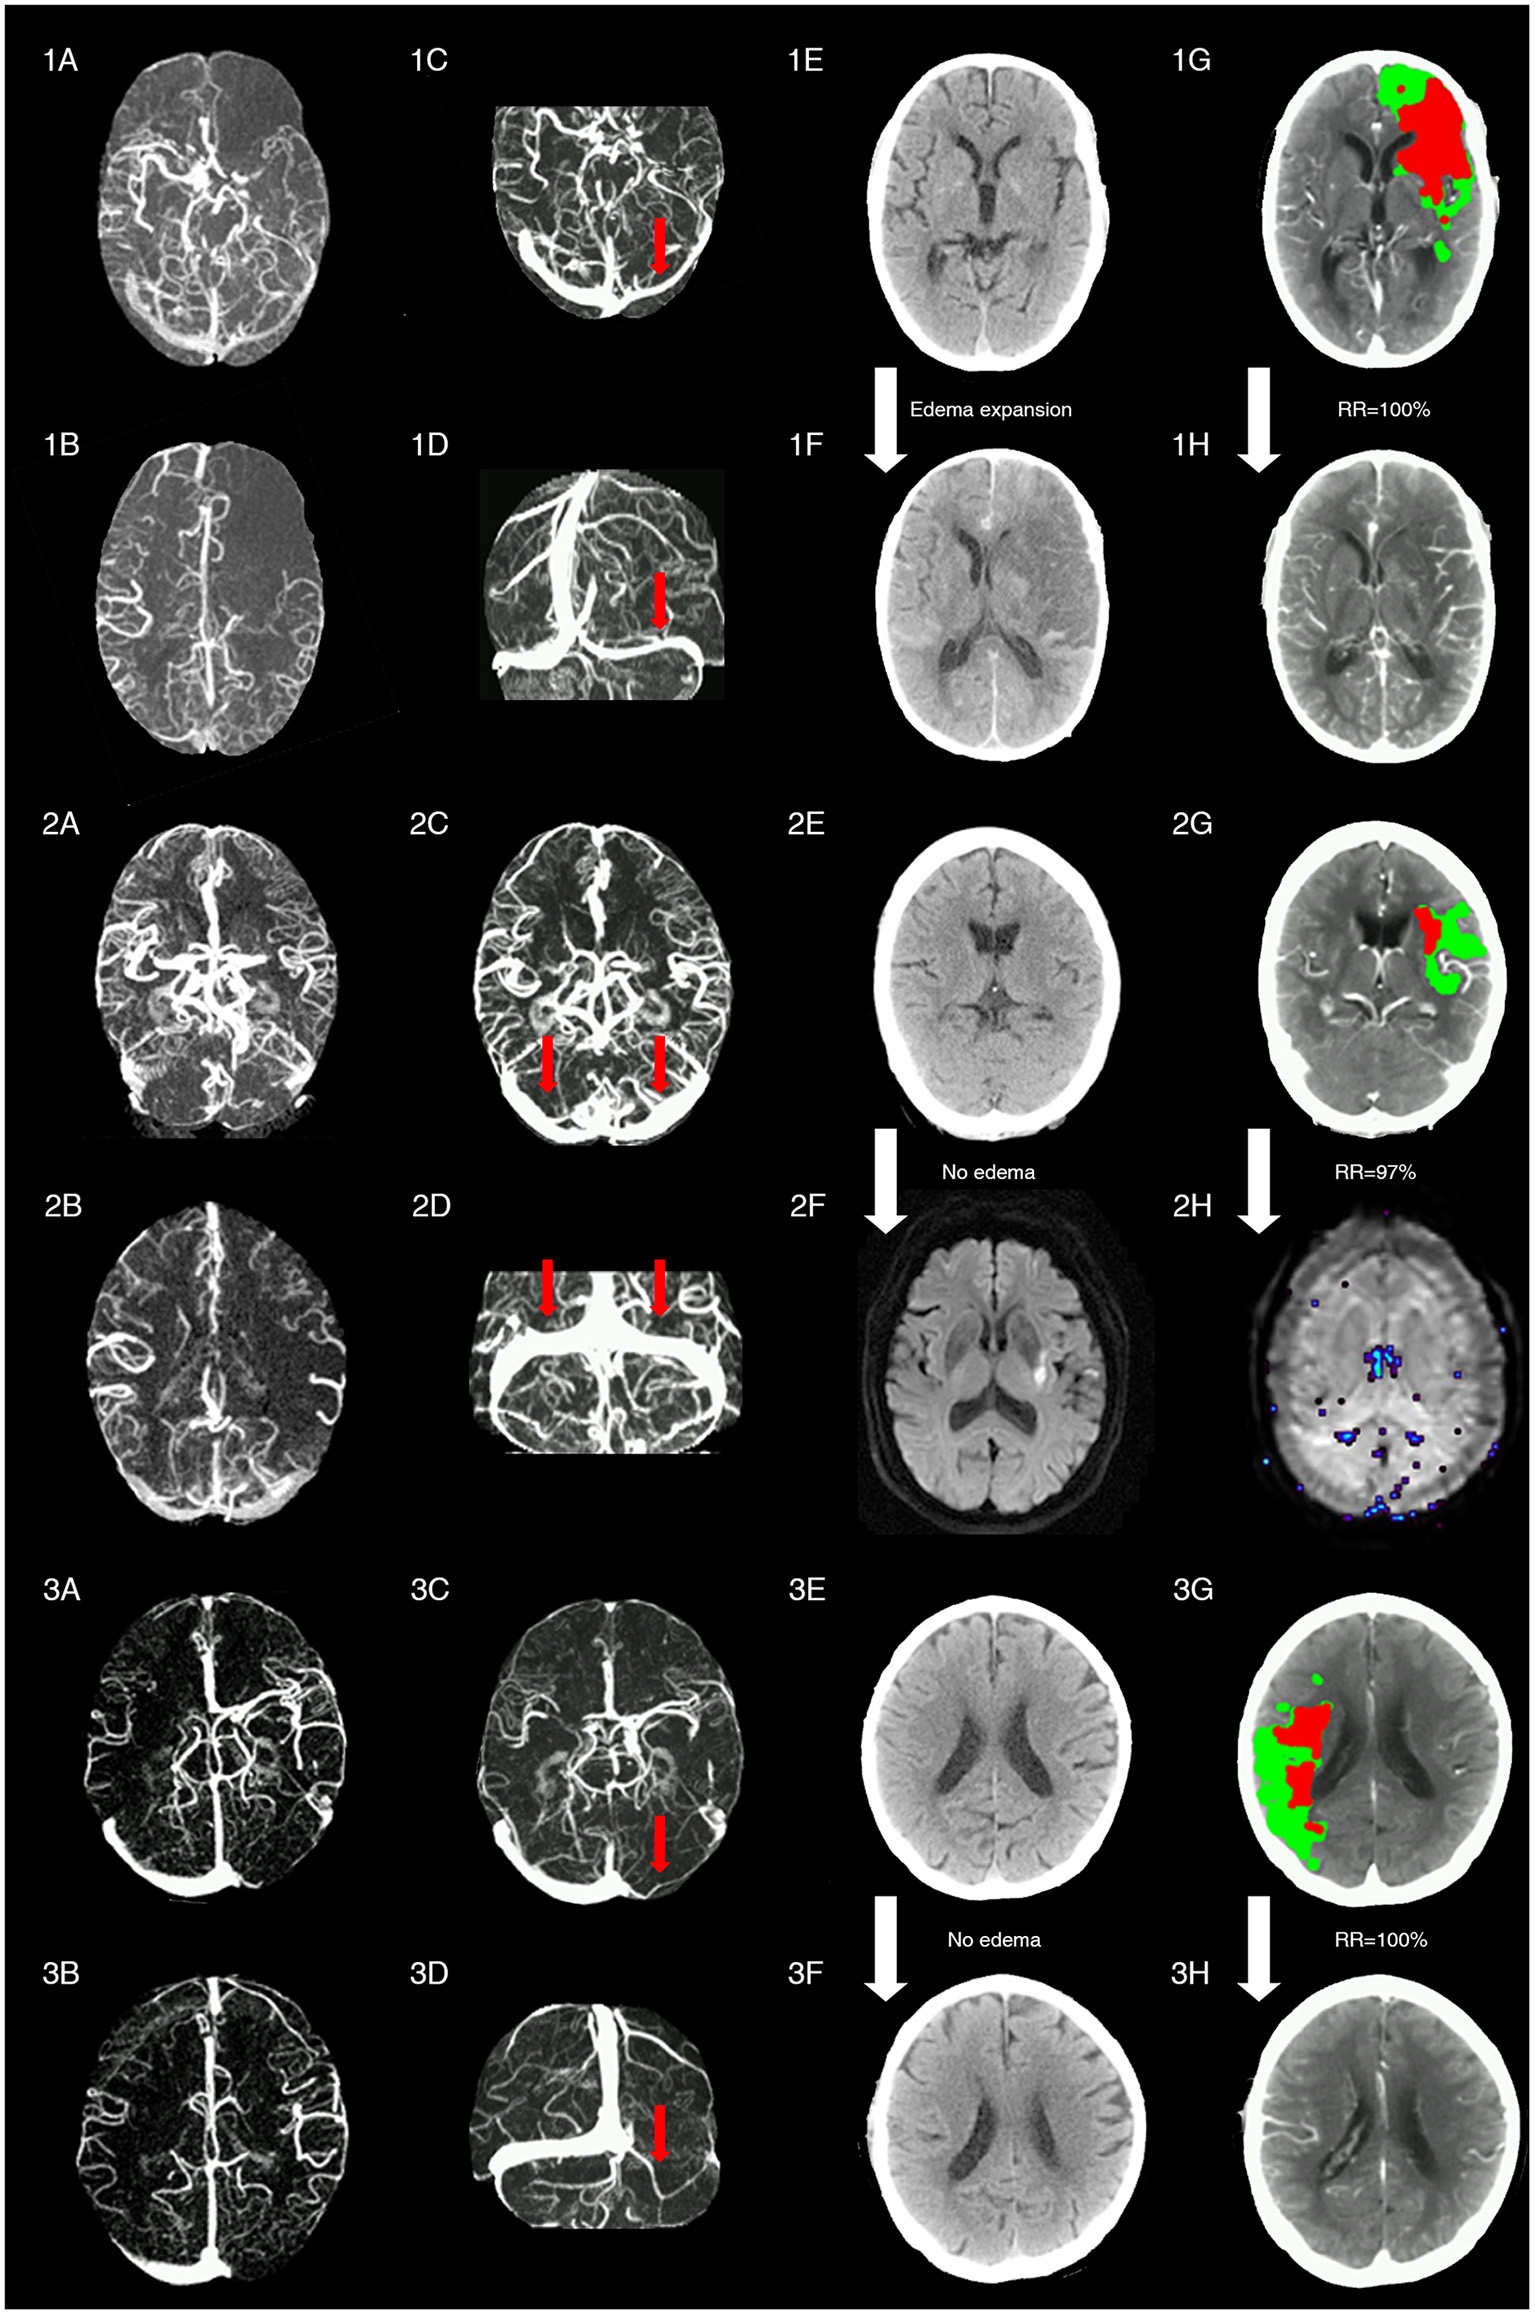

Figure 4 shows three cases with representative images.

Figure 4

Representative images of patients with different status of ipsilateral transverse sinus and collaterals. Patient 1 with acute left middle cerebral artery occlusion (MCAO) (baseline NIHSS = 14) presented with poor collaterals [integrated collateral grading scale (CGS) =0] (1A,1B) and FDITS (the red arrow in 1C,1D) on 4-dimensional computed tomographic angiography (4D-CTA). The patient received intravenous thrombolysis bridging with endovascular therapy at 2.5 h from stroke onset. At 24 h after reperfusion therapy, this patient developed brain edema expansion on non-contrast CT (NCCT) from baseline score 0 (1E) to 2 (1F), although reperfusion rate was 100% with hypoperfusion (red plus green area) volume changing from 220 ml (1G) to 0 ml (1H) on lesion map. The modified Rankin scale (mRS) score was 4 at 3 months. Patient 2 with acute left MCAO (baseline NIHSS = 13), presented with good collaterals (CGS = 2) (2A,2B) and symmetric bilateral transverse sinuses (non-FDITS) (two red arrows in 2C,2D) on 4D-CTA. The patient received intravenous thrombolysis at 4 h from stroke onset. At 24 h after reperfusion therapy, this patient developed no brain edema with edema score keeping 0 from baseline NCCT (2E) to 24-h diffusing weighted imaging (DWI) (2F), and reperfusion rate was 97% with hypoperfusion (red plus green area) volume changing from 29 ml (2G) to 1 ml (2H) on lesion map. The mRS score was 0 at 3 months. Patient 3 with acute right MCAO (baseline NIHSS = 11), presented with good collaterals (CGS = 2) (3A,3B) and filling defect of contralateral transverse sinus (FDCTS) (the red arrow in 3C,3D) on 4D-CTA. The patient received intravenous thrombolysis bridging with endovascular therapy at 2 h from stroke onset. After reperfusion therapy, this patient developed no brain edema with edema score keeping 0 on NCCT from baseline (3E) to 24 h (3F), and reperfusion rate was 100% with hypoperfusion (red plus green area) volume changing from 137 ml (3G) to 0 ml (3H) on lesion map. The mRS score was 0 at 3 months.